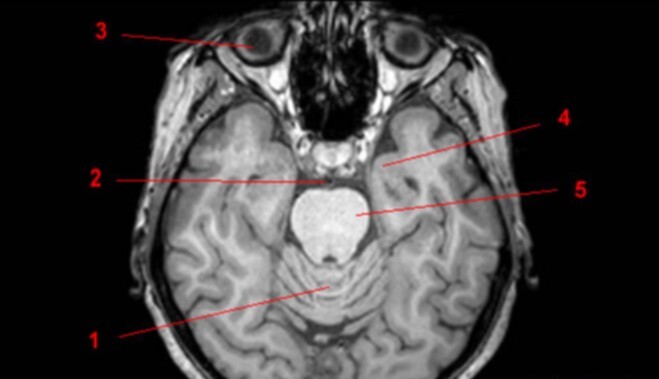

8

Q

Label 1-5

A

1. Vermis of cerebellum

2. Basilar artery

3. Rt globe of eye

4. Lt temporal lobe

5. Pons